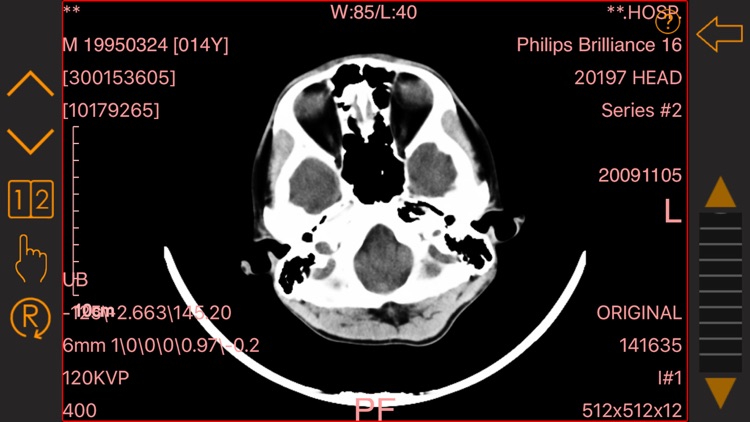

医学影像查看:可查看标准dicom格式的医疗影像。

医学影像查看:可查看标准dicom格式的医疗影像。

医学影像查看:可查看标准dicom格式的医疗影像。